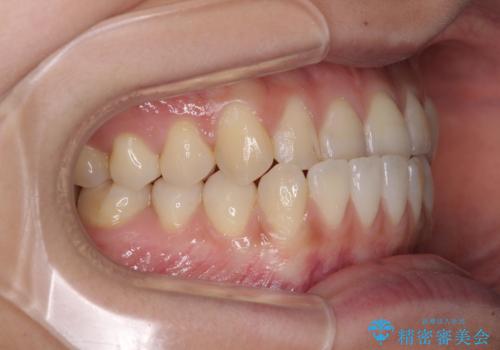

前歯のクロスバイトを治したい ワイヤー装置による矯正治療

- 前歯の反対咬合を気にして来院された患者様です。

マウスピース矯正も提案しましたが、しっかりと使用する自信がないとのことで、ワイヤー装置により矯正治療を行うこととしました。

クロスバイト改善まではスムーズに進みましたが、その後は強い舌の突出癖によりオープンバイトの期間が長く続きました。

舌のトレーニングをしっかりと実施してもらい、何とか仕上げることができました。